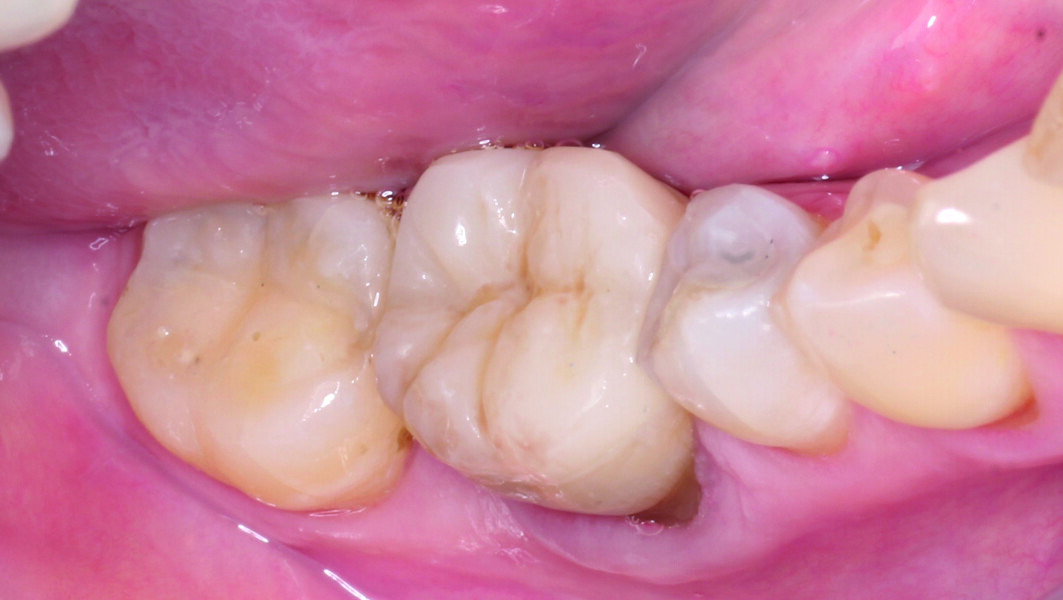

Results and discussion The fully aesthetic and functional results were remarkable and were achieved in a single chairside session, to the full satisfaction of both patient and dentist (Figs. 16–19).

This patient was treated with an endocrown because of the impossibility of a direct restoration owing to the insufficient thickness of the remaining walls 16 years after root canal treatment. This helped avoid unnecessary loss of healthy tooth structure, was time-saving, as post-endodontic treatment with a build-up followed by a regular ceramic overlay would have required multiple sessions, and had a lower cost of the treatment for the patient.

Restoration with an endocrown posed a lower risk of chemical failure owing to fewer adhesive interfaces. In the case of a build-up and overlay, we would have had two adhesive interfaces (dental tissue to build-up and build-up to crown or overlay), instead of just one (dental tissue to endocrown). Similarly, there was a lower risk of biomechanical failure of an endocrown than with more invasive preparation, for example with metal posts.

The most recent scientific evidence demonstrates that milled CAD/CAM composite resin endocrowns are not only a more conservative approach but also more stable over time than ceramic indirect restorations. When restoring endodontically treated teeth, endocrowns produced using composite resin materials showed more uniform stress distribution and higher fracture resistance.